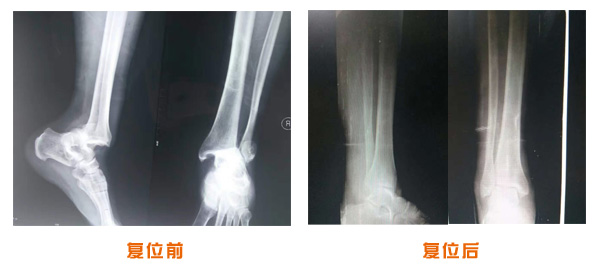

復位前后對比

肘關(guān)節(jié)脫位骨折治療前后對比